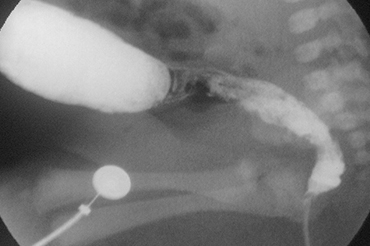

Enfermedad de Hirschsprung